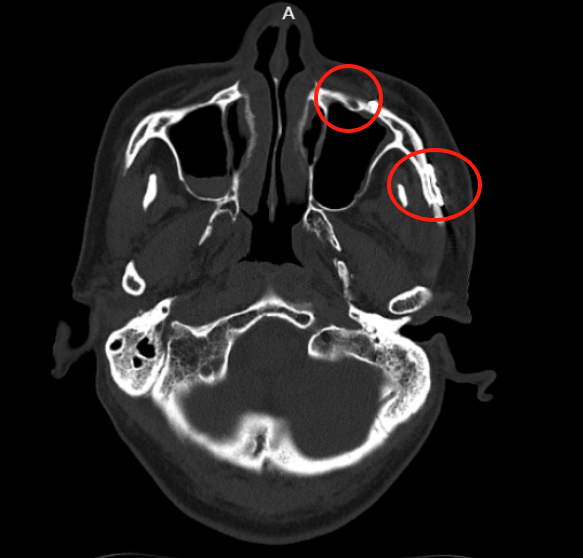

术后一周,张师傅复查CT显示:骨折断端对位良好,内固定物位置稳定,未见松动或移位,颞下颌关节结构正常,关节间隙对称。目前张师傅面部恢复情况良好。